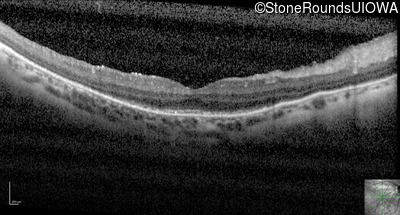

Optical Coherence Tomography - Left - 20/50 +1

Exemplar / OCT Stack